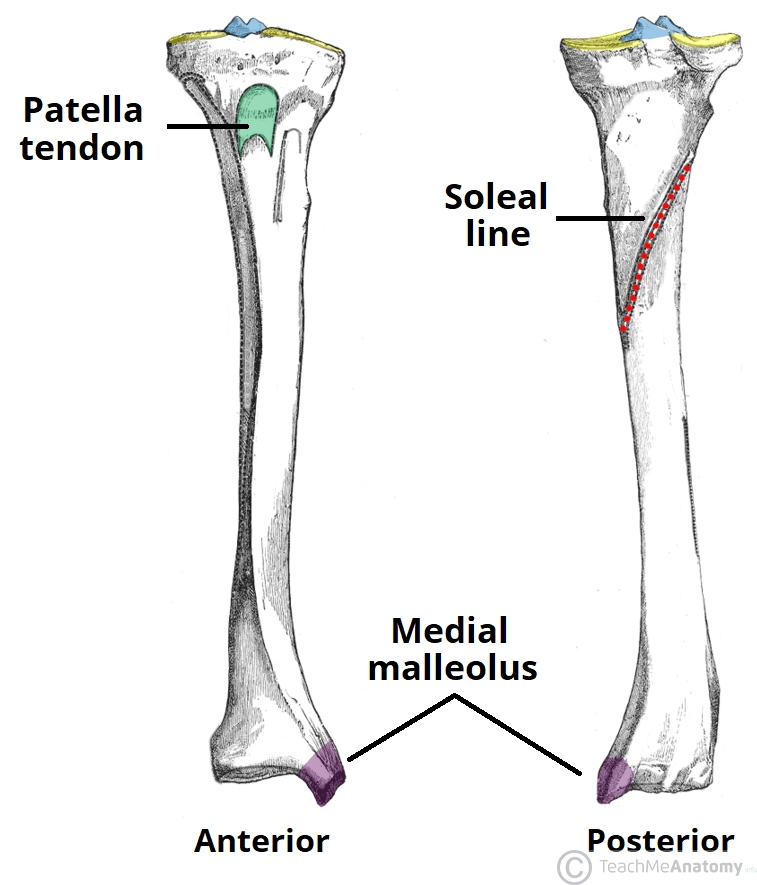

The Tibia – Proximal – Shaft – Distal – TeachMeAnatomy